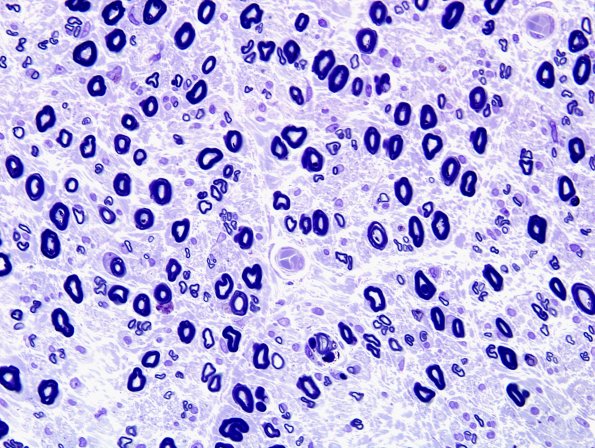

There is moderate loss of large myelinated axons with a significantly decreased population of small myelinated axons which are present mostly as regenerative clusters